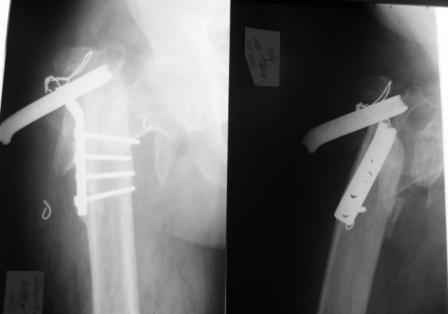

Доброго времени суток! В клинику обратился пациент П., 40 лет с несросшимся чрезвертельным переломом левого бедра, состояние после остеосинтеза Г-образной пластиной, перелом фиксатора. Из анамнеза известно, что травма в 2004 году - лечился консервативно. В течение 2 -х лет наблюдался у травматолога по месту жительства - перелом не сросся. В 2006 году пациенту выполнен остеосинтез несросшегося чрезвертельного перелома левого бедра Г-образной пластиной.В течение 3 -х лет пациент ходил с дозированной нагрузкой на оперированную конечность. В ноябре 2009 года почувствовал резкую боль в области операции, отмечал нестабильность, утрату опороспособности. При осмотре укорочение конечности 7 см. Коллеги, необходимы ваши рекомендации в лечении данного вида последствий травмы. На КТ диагноз подтвержден.

Интересно было бы увидеть снимки после операции (думаю у больного что-то да и сохранилось).

По теме: фрагменты пластины полюбому надо удалять. После удаления сходу заменить ее на что-то более существенное. Возможно тут подойдет фиксатор DHS. (Подозреваю что на конструкции подороже денег у пациента может и не оказаться). На счет эндопротезирования - опыта не имею... поэтому оставлю этот вопрос без коментариев.

По моему мнению, оптимальным методом лечения, в данном случае является эндопротезирование тазобедренного сустава. Лучше использовать т.н. ревизионные" имплантаты типа Вагнера, Helios и т.п. С уважением.

Если в течение 6 лет не произошел асептический некроз головки, то почему же он произойдет после операции DHS системой? Я думаю, что на самом деле, учитывая возраст пациента, оптимальный будет вариант органосохраняющей операции, т.е DHS или гамма гвоздь. С уважением

Уважаемый Нурмет Термирханов, вы серьезно считаете что после 6 лет такого положения проксимального отдела бедра, там есть еще что сохранять? К сожалению качество снимка не позволяет судить о степени дегенерации в суставе, но можно смело предположить, что ДА там уже "цветет" в полную силу.А еще локальный остеопороз (нагрузка не адекватная), а еще металлоз (металлоконструкция не стабильная). Кроме того посттравматическая контрактура (куда без неё при таком стояние отломков). После манипуляций по репозиции, достаточно агрессивных (лигоментотаксис здесь не поможет)и дополнительных отверстий -каналов в головке - все предпосылки для АН последней. Впрочем, для дальнейших проблем больного достаточно и остеоартроза. Как раз артропластика и является для больного органосохраняющей, так как восстанавливает не только орган (конечность), но и его функцию (движение и опороспорсобность), причем в относительно короткие сроки. Вы же предлагаете сохранить не орган, а часть его, причем уже компремированную, с сомнительной перспективой длительного хождения с костылями (остеопороз!)и ограничения движения в суставе (ликвидировать контрактуру одним восстановлением костной анатомии через 6 лет маловероятно) и болевым синдромом, обусловленным двумя предыдущими причинами.

Уважаемые коллеги, учитывая возникшие вопросы по определению дальнейшей тактике лечения, выкладываю томограммы.